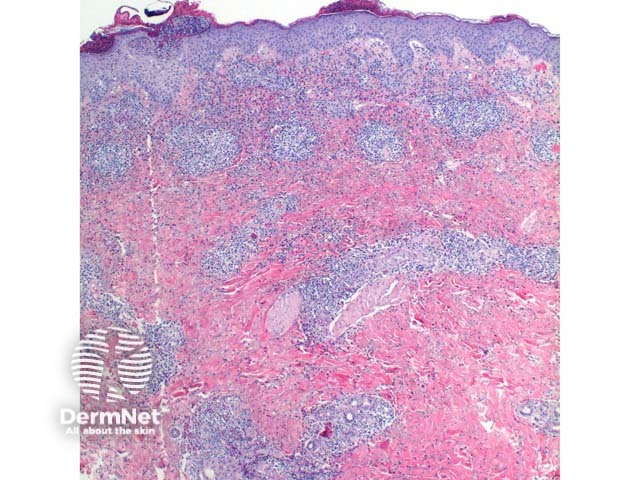

Scanning power view of scabies shows a pattern of an epidermal and wedge shaped dermal inflammatory process (Figure 1). The epidermis may show significant scale crust comprised of serous exudate, neutrophils, and eosinophils (Figure 2). There may be focal ulceration or erosion secondary to excoriation. The inflammatory infiltrate may show a wedge shaped or diffuse superficial and deep perivascular and interstitial pattern. Lymphocytes with numerous eosinophils are the rule with scattered superficial neutrophils seen in excoriated or impetiginised cases. Deep interstitial eosinophils are an important clue to an arthropod bite reaction (Figure 3).

Figure 1